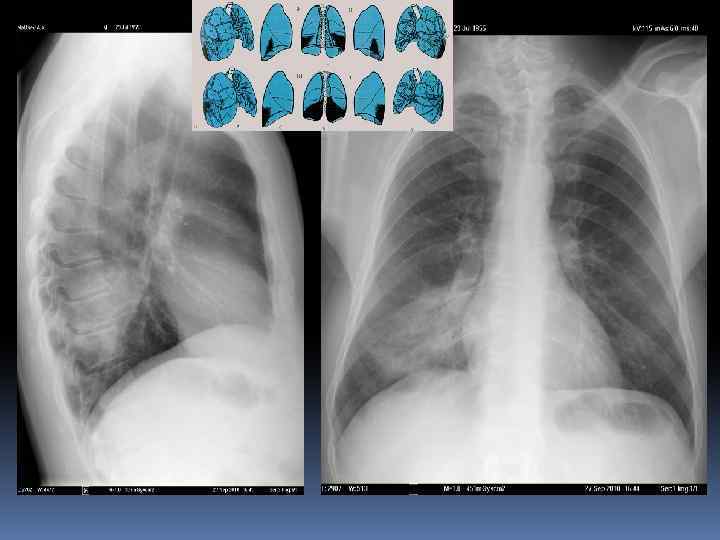

Легкие. Проекция долей легких. Правое легкое: две междолевые щели делят легкое на три доли. Левое легкое имеет две доли Пространственное расположение междолевых щелей. Топография долей легкого.

Анатомия ОГК. Пневматизация. Плевра. Междолевые борозды.

Междолевые борозды. Борозда между нижней и верхней, средней долями справа и верхней и нижней долями слева - главная междолевая борозда, имеется с обеих сторон. Справа между верхней и средней долями расположена дополнительная, малая горизонтальная междолевая борозда. Борозды бывают неполными, могут встречаться дополнительные борозды, образующие доли. Борозда состоит из двух слоев плевры, между которыми имеется потенциальная щель. В месте перехода грудной стенки в диафрагму, слои плевры образуют острый угол – синус (заворот): реберно диафрагмальный, реберно – медиастинальный. Задние реберно-диафрагмальные синусы самые глубокие, вытянуты в каудальном направлении.

Междолевые борозды.